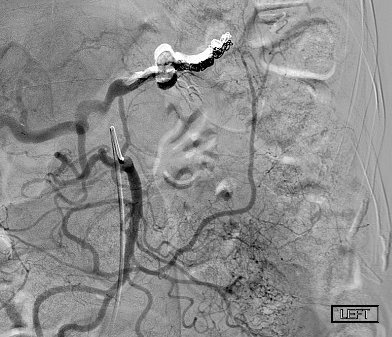

@dpduncanMD_IR @VUMCradiology @UCSDRadRes @Quinn_Meisinger @myliuMD @shelbyfrantzMD @iRadRock @MinaMakaryMD @theIIMD @IRdocAndy @JohnDoIR @RmelikMD @TWongMD @DRimaniIR @danbrownIO @ecemmons @CBoonie_nanoIR @Ajairam_MD_IR pubmed.ncbi.nlm.nih.gov/35907643/ I’ve always thought this was a great case. Great technique by the IR to boot!